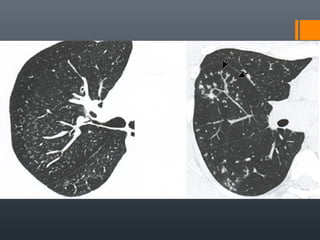

O documento discute vários conceitos radiológicos incluindo consolidação, atelectasia, nódulos, pseudocavidades e padrões intersticiais, fornecendo definições, sinais e diagnósticos diferenciais para cada tópico. Ele também discute a redução da atenuação pulmonar e fornece um link para mais informações.